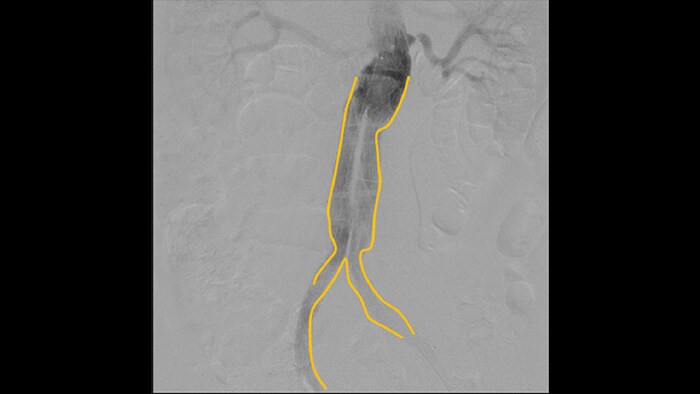

A angiografia por subtração digital (ASD) é usada em procedimentos vasculares intervencionistas para visualizar os vasos sanguíneos com clareza, removendo estruturas que podem obscurecer a visibilidade dos vasos. A fluoroscopia do roteiro sobrepõe uma imagem com contraste subtraída adquirida anteriormente à fluoroscopia ao vivo, permitindo que você monitore um dispositivo sem reinjetar contraste.

Use a ferramenta Contorno para marcar com facilidade uma bifurcação ou ramos laterais, simplesmente desenhando no monitor da Estação de Visualização Portátil com o dedo ou um mouse conectado externamente.